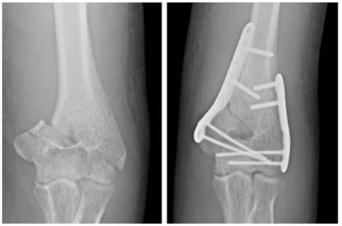

Um paciente de 30 anos de idade foi vítima de queda de árvore há cerca de um dia, sofrendo trauma no cotovelo esquerdo. Foi atendido no pronto-socorro e solicitadas as radiografias retratadas nas figuras.